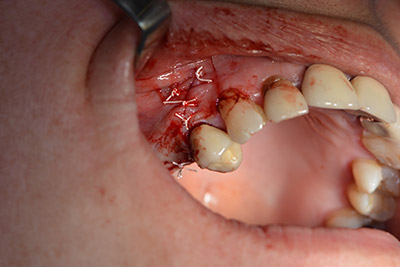

An absorbable membrane was used as the barrier in the buccal direction and covered the augmentation. Finally, saliva-proof sutures were placed (Fig. 15 to 19).